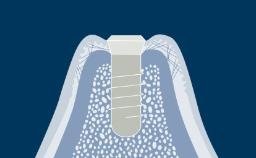

Once a tooth has been removed, dynamic physiological and dimensional changes take place during the healing phase that may influence the choice of the best time to place an implant.

There are several time points following tooth extraction that may be considered for the placement of dental implants. Each time point has advantages and disadvantages.

The clinician is in a unique position to be able to prescribe the time for implant placement following tooth extraction in order to maximize the advantages and to achieve successful long-term outcomes. An understanding of the factors that are important in determining the timing of implant placement is an essential part of the treatment planning process. These factors will be presented in this module.